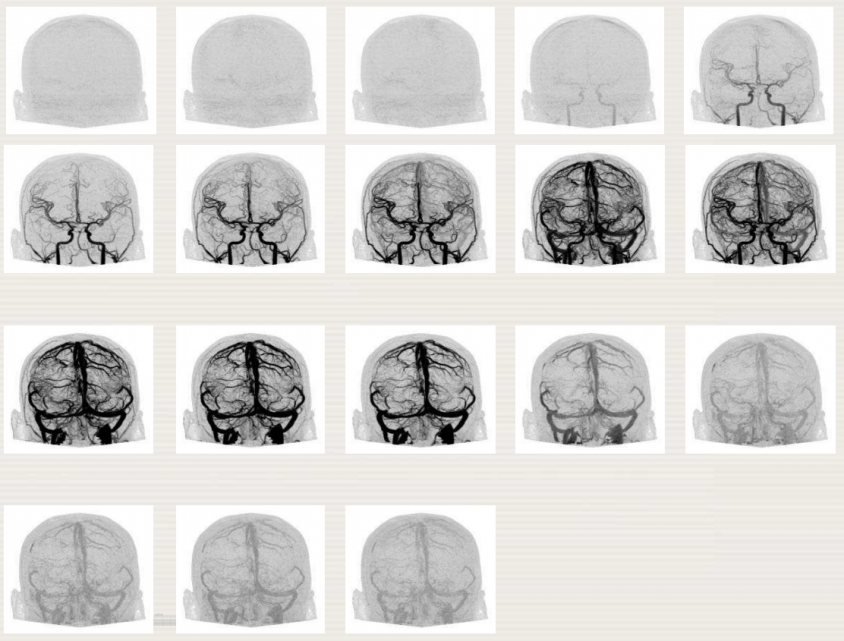

The IAEA has recently published the ‘Diagnostic Radiology Physics: A Handbook for Teachers and Students’, aiming at providing the basis for the education of medical physicists initiating their university studies in the field of diagnostic radiology. This has been achieved with the work of 41 authors and reviewers from 12 different countries. The 24 chapters include a broad coverage of topics relevant to diagnostic radiology physics, including the radiation physics, dosimetry and instrumentation, image quality and image perception, imaging modality specific topics, recent advances in digital techniques and radiation biology and protection. This book teaches the essential physics of diagnostic radiology and its application in modern medicine. It is not designed to replace the large number of textbooks available on many aspects of diagnostic radiology physics, which will still be necessary to deepen knowledge in the specific topics reviewed here. It is expected to successfully fill a gap in the teaching material for medical radiation physics in imaging, providing in a single manageable volume the largest possible coverage available today.

Additional training material, in the form of PowerPoint presentations, has been developed for each chapter of the handbook. They are designed, as an additional training tool to assist in the better presentation of the content of each chapter. The finalized peer-reviewed slides are available here as PDF files and PowerPoint.